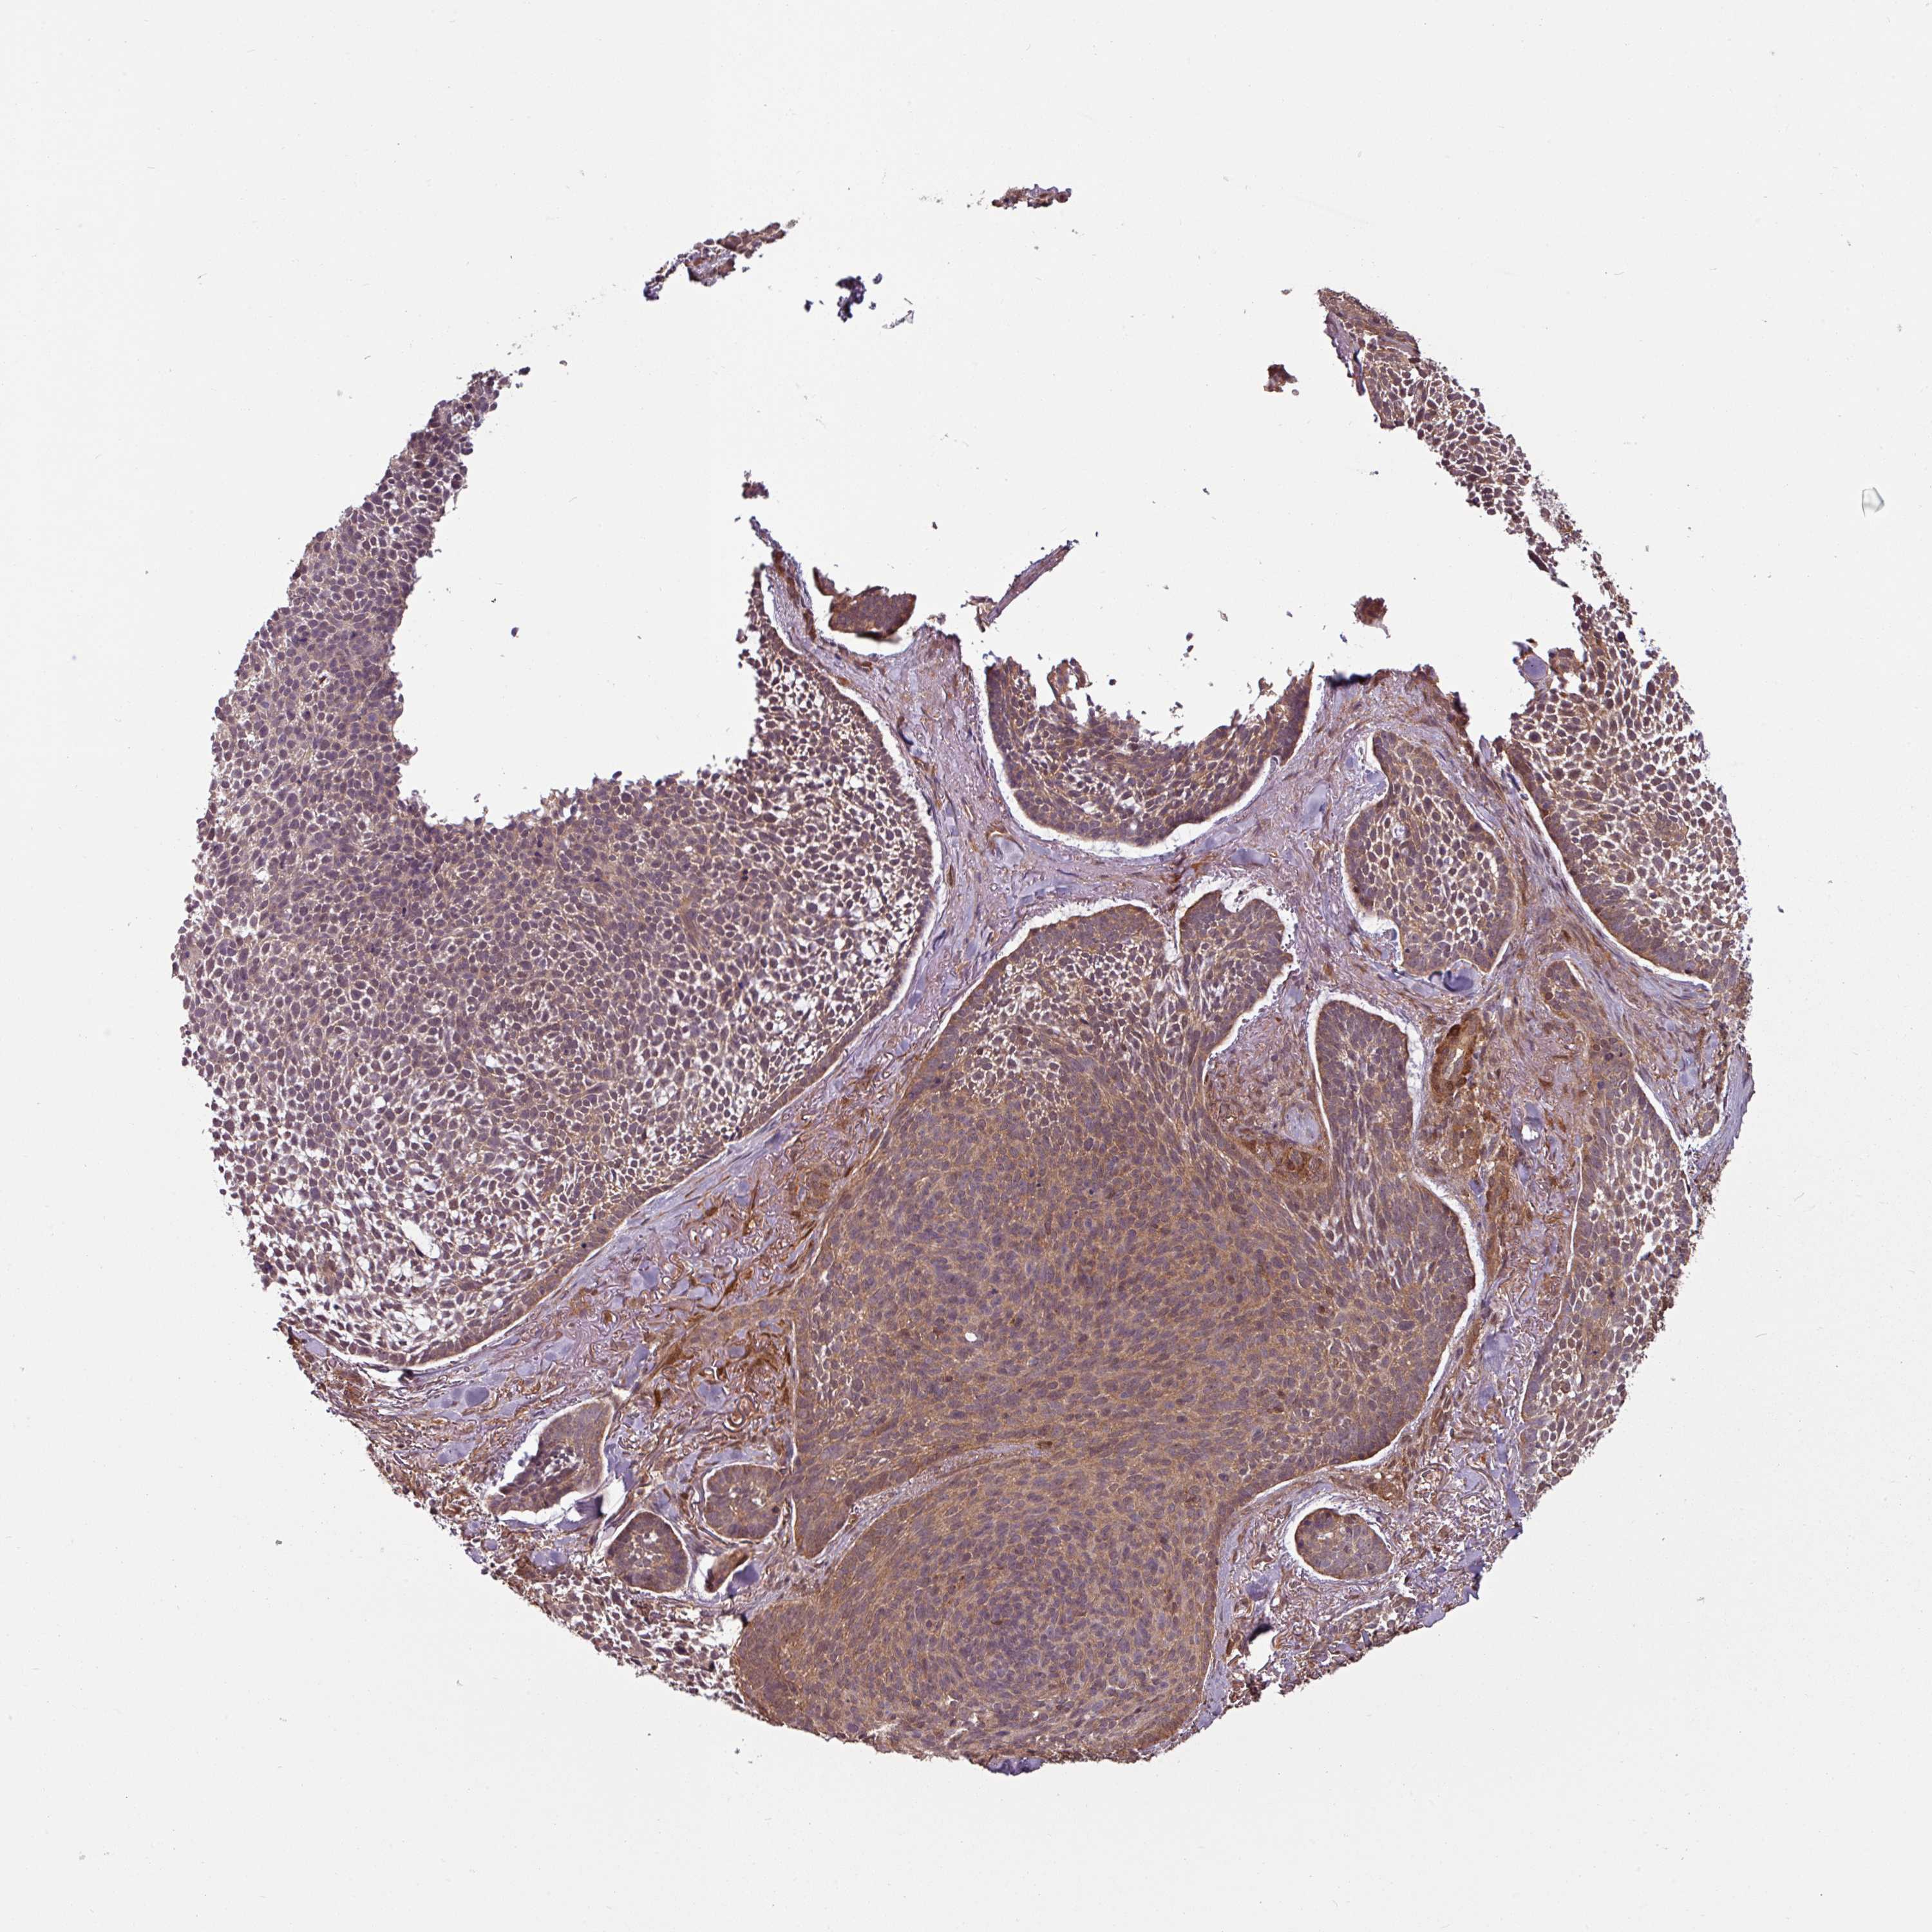

SKIN CANCER - Protein expressioni

A mouse-over function shows sample information and annotation data. Click on an image to view it in a full screen mode. Samples can be filtered based on level of antibody staining by selecting one or several of the following categories: high, medium, low and not detected. The assay and annotation is described here.

Antibody staining in the annotated cell types in the current human tissue is reported as not detected, low, medium, or high, based on conventional immunohistochemistry profiling in selected tissues. This score is based on the combination of the staining intensity and fraction of stained cells.

Each image is clickable and will lead to virtual microscopy that enables deeper exploration of all samples and also displays staining intensity scores, fraction scores and subcellular localization as well as patient and tissue information for each sample.

Antibody HPA051248

Staining

High

Intensity

Strong

Location

Nuclear

Cytoplasmic/membranous

Basal cell carcinoma

Squamous cell carcinoma, NOS

Squamous cell carcinoma, metastatic, NOS